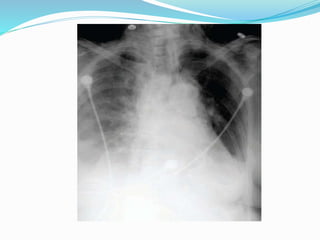

 THORACIC : MEDISTINAL / ANTERIOR CHEST

WALL ALON THE SPINAL NERVES

• CHEST X-RAY

 WIDENED MEDIASTINUM

MEDISTINAL WIDENING

 CHEST X RAY : FOR PULMONARY TB

COLD ABSCESS  1.PARAVERTEBRAL ABSCESS : A SOFT TISSUE SHADOW CORRESPONDING TO AFFECTED VERTEBRA.  WIDENED MEDIASTINUM  RETROPHARYNGEAL ABSCESS  PSOAS ABSCESS

GENERAL INVESTIGATIONS  ESR MANTOUX  ELISA : ANTI TB ANTIBODY  CHEST X RAY : FOR PULMONARY TB